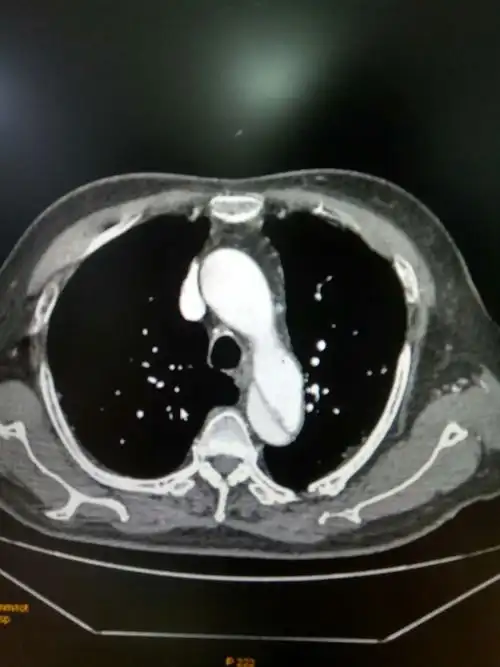

主动脉夹层

主动脉夹层3hdf.jpg